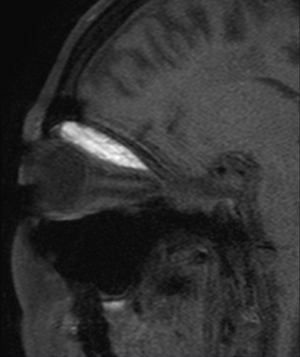

Orbital subperiosteal hemorrhage is caused by rupture of diploic veins between the periosteum (periorbita) and the bony orbit. Rupture causes a local hemorrhage with subsequent hematoma formation between the periorbita and bone. The space-occupying blood increases pressure, causing the periorbita to peel away from the bone. If the periorbita remains intact blood will not enter the orbit and imaging will reveal a bilenticular shape to the hematoma. An untreated orbital subperiosteal hematoma may enlarge over time or spontaneously resolve. A 2013 case series[14] found that 9 of 11 patients with CT-confirmed orbital subperiosteal hematomas displayed a superior orientation within the orbit.

The clinical diagnosis of OSH rests on the combination of physical exam findings and confirmatory imaging. The most common location is a superior and medial orientation of the hematoma involving the orbital plane of the frontal bone. [6][10] Non-contrast CT is the imaging modality of choice due to its capacity to highlight blood between the periosteum and bony orbit. CT imaging has the advantage of distinguishing acute from subacute or hyperacute states on the basis of signal intensity.[15] MRI is inferior due to difficulty in distinguishing boney structures but this modality can highlight such hematomas as hypointense on T1-weighted imaging and hyperintense on T2-weighted imaging. CT and MRI are superior to ultrasound imaging, and orbital plain films have no role in diagnosis. In idiopathic cases of non-traumatic OSH, a pathologic assessment of the evacuated fluid can determine whether the hematoma is of hematologic or neoplastic origin.